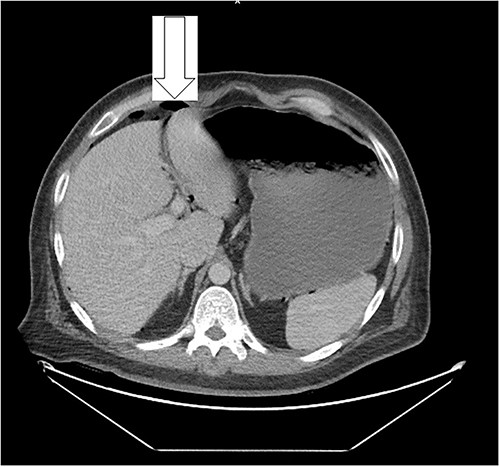

Ten days after discharge, he was readmitted with the same symptoms of nausea and vomiting. The CT showed pneumoperitoneum (see Fig. 2) again with another EL with consequent negative results and no viscus perforations. Lesser amounts of free fluid in both upper quadrants and in the pelvis were noted. These findings remain suspicious for a perforated viscus. Few days later, the patient reported feeling better and was discharged.